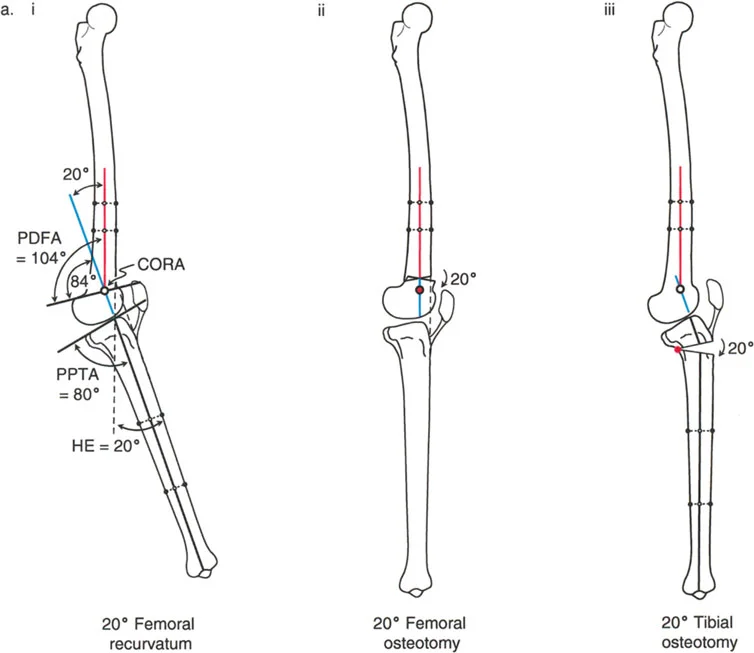

- الأشعة السينية الطويلة للطرف السفلي بالكامل أثناء الوقوف (Standing Long-Leg AP View): تُعد هذه الأشعة حاسمة لتقييم المحاذاة الميكانيكية للطرف السفلي بأكمله. تُظهر بدقة درجة الانحراف الأفحج (Varus) أو الأروح (Valgus) وتساعد في تحديد مركز دوران التشوه (CORA).

تصحيح الركبة الارتدادية (Recurvatum Deformity - Hyperextension)

- قطع العظم الانثنائي (Flexion Osteotomy):

- إذا كان التشوه عظميًا (تقوس خلفي)، يتم إجراء قطع عظم انثنائي في عظم الفخذ أو الساق لتصحيح الارتدادية.

- الأستاذ الدكتور محمد هطيف يشدد على أهمية عدم استخدام قطع عظم الفخذ الانثنائي لتصحيح ارتدادية الساق، والعكس صحيح، لتجنب الانزلاق الخلفي أو الأمامي للركبة.

- اعتبارات خاصة: في المرضى الذين يعانون من ضعف عضلي (مثل شلل الأطفال)، قد يحتاج التصحيح إلى فرط تصحيح بسيط (overcorrection) إلى وضعية انثناء لضمان ثبات الركبة ومنع فرط البسط غير المتحكم فيه.